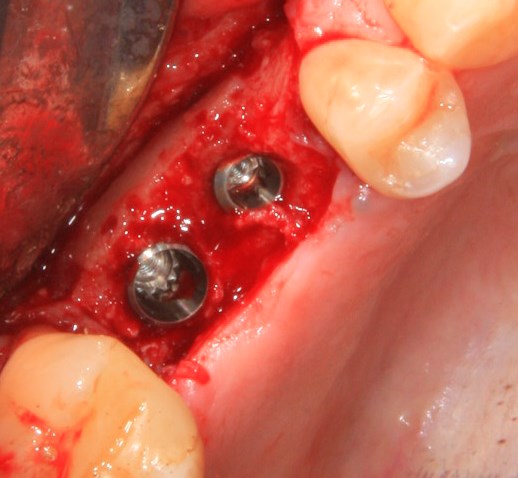

К установке имплантов можно приступать через 3-4 месяца (рис 52, 53):

Рисунок 52, 53. Установка импланта через 3 месяца после удаления зуба и синуслифтинга: слева – скелетирование верхней челюсти, справа – установленный имплантат.